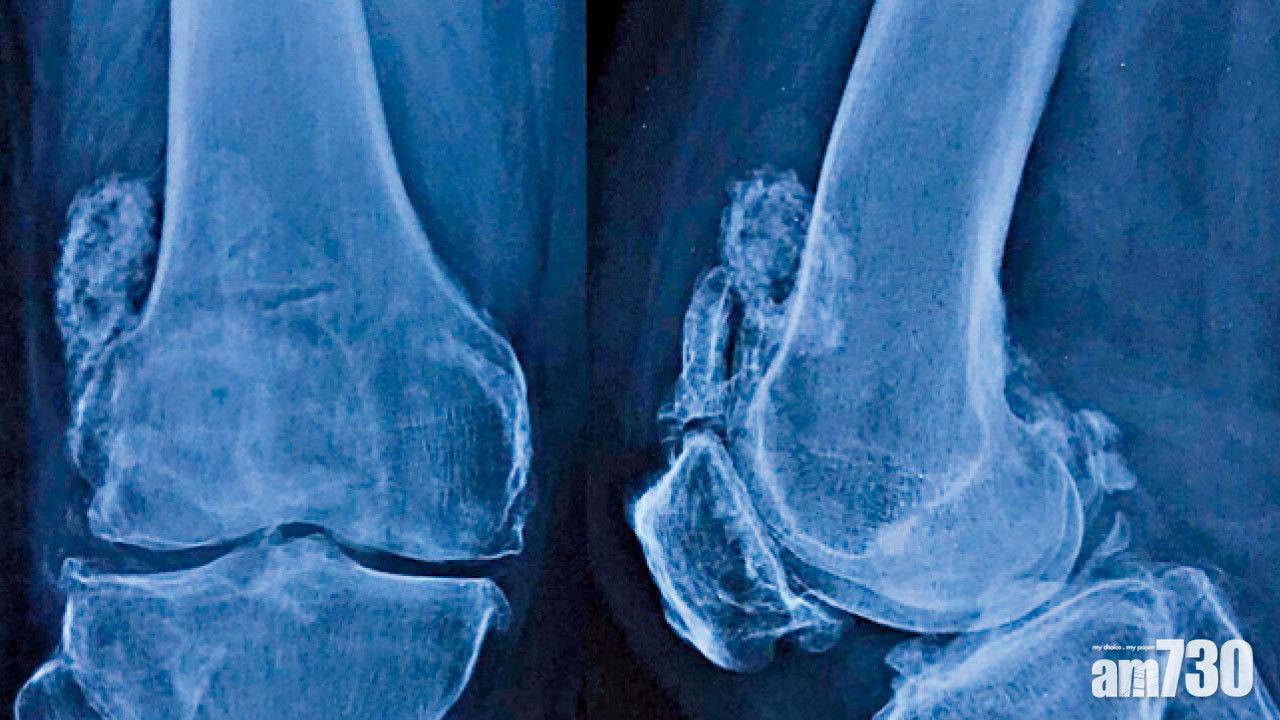

走路出現膝內側和前膝痠痛,是早期膝關節退化的症狀。及後當軟骨磨蝕,而令骨骼出現耗損和增生骨刺,更會造成膝關節腫脹、變形(O形腿)和僵硬(不能完全伸直和屈曲),令患者不能再久站、跑步和蹲下。X光能評估膝關節退化程度,按其嚴重性一般可分為四期;而磁力共振則可發現早期的軟骨磨蝕、勞損性半月板撕裂和滑膜炎等。